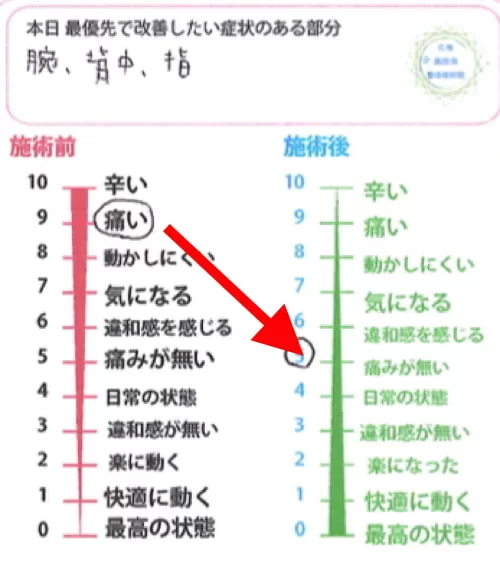

施術前後のアンケート

腕・背中・肩の痛み

施術前 9:痛い → 施術後 5:痛みがない